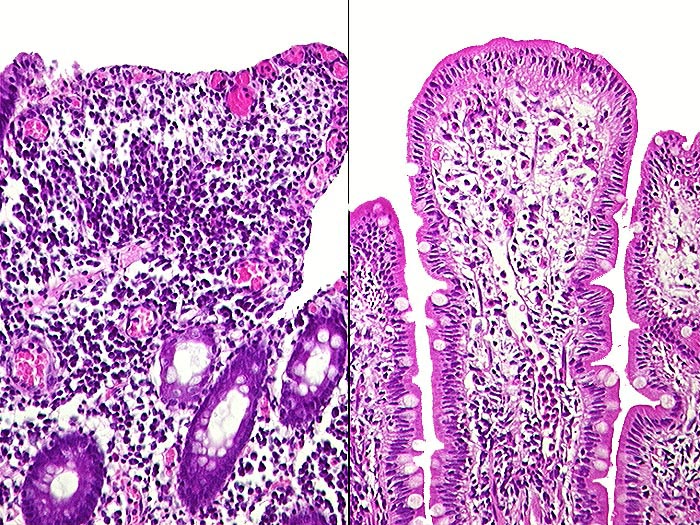

PathoPic ID 409 - Florider Morbus Crohn

Florider Morbus Crohn

Beide Bilder stammen aus derselben Biopsie der Dünndarmanastomose. Rechts praktisch normale Dünndarmschleimhaut. Links verplumte oberflächlich erodierte Zotten.

St.n. Ileozökalresektion vor 20 Jahren wegen Morbus Crohn. Rezidivierter Dünndarmileus.